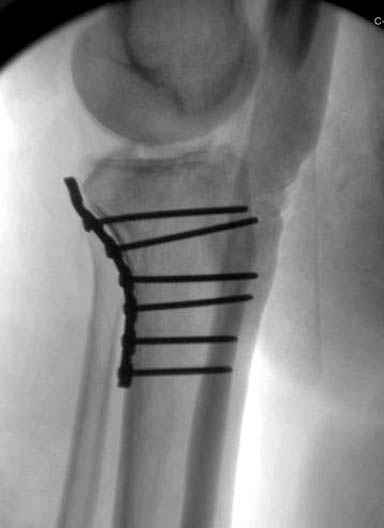

Трудно поверить, что разрекламированная Ортопедическая школа Восточной Украины позволяет такие странные снимки? На прямом снимке сохранен общий контур плато, но не известна судьба импрессии суставной поверхности. На полубоковой?, оставлен без репозиции задне-медиальный отдел, и навряд ли после такой фиксации можно удовлетвориться результатом.

Такая ситуация характерна для многих, когда принимается ошибочное решение, т.е пытаются фиксировать одним имплантом переломы двух мыщелков. Латеральная пластина приемлема только для тех случаев, когда сохраняется интактным медиальный диафизарный кортекс и отсутствует фрагментация на верхушке медиального перелома.

Здесь как раз тот случай, когда результат зависит не только от мастерства хирурга, но и от наличия современных методов исследования. Например, КТ которая поможет рассчитать направления шурупов и установку импланта. Кроме этого, поможет определиться с доступом.